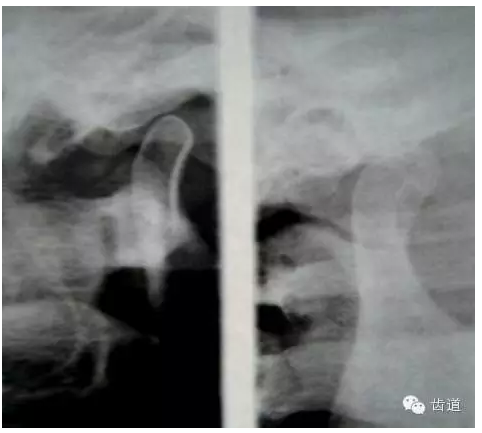

2.關(guān)節(jié)放射線平片或斷層片

— 關(guān)節(jié)間隙改變

3.關(guān)節(jié)造影 主要是上腔造影

— 顯示關(guān)節(jié)盤移位,穿孔。

5.x-ray檢查:平片上可見有三種類型:

第一種類型是正常關(guān)節(jié)解剖結(jié)構(gòu)形態(tài)消失,關(guān)節(jié)間隙模糊,關(guān)節(jié)窩及髁狀突骨質(zhì)有不規(guī)則破壞,多為纖維性強(qiáng)直。

第二種類型是關(guān)節(jié)間隙消失,髁狀突和關(guān)節(jié)窩融合成很大的致密團(tuán)塊,呈球狀。

第三種類型是致密的骨性團(tuán)塊可波及下頜切跡,使正常喙突,顴弓,下頜切跡影像消失。